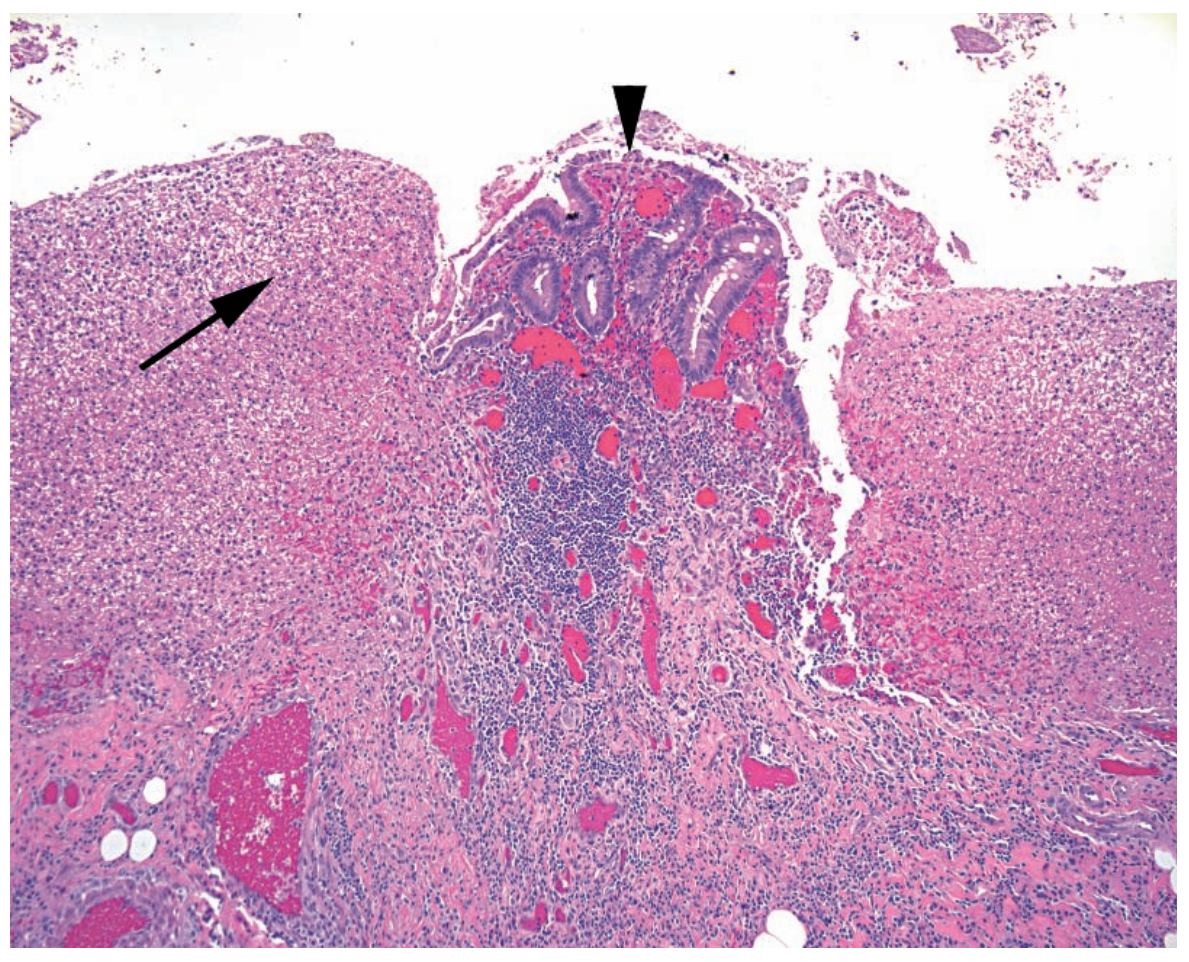

Q

A

Cholesteatoma

Arrow: Thin epithelium surrounding the keratin debris